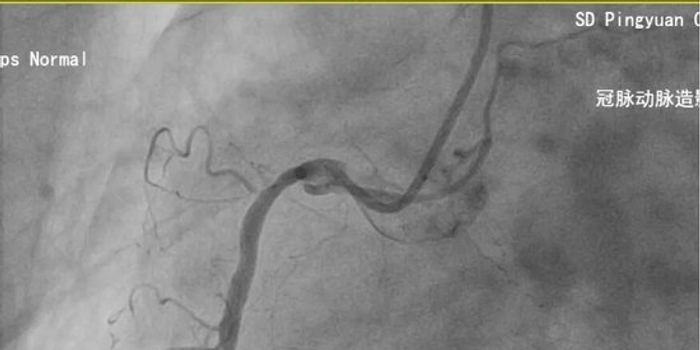

61岁的王先生因“阵发性上腹部不适”就诊,检查发现竟是凶险的急性前壁心肌梗死。择期冠脉造影结果让在场的医生都捏了一把汗:左主干+三支病变。这意味着患者的心脏供血,如果不及时干预,随时可能发生猝死。

面对这一介入领域的“硬骨头”,平原县人民医院心内科团队迎难而上,在左主干-前降支的关键病变处精准植入支架。术后造影显示,狭窄解除,血流恢复,患者转危为安。这例手术的成功,标志着该科在处理复杂高危冠脉病变方面达到了一个新的技术高度。